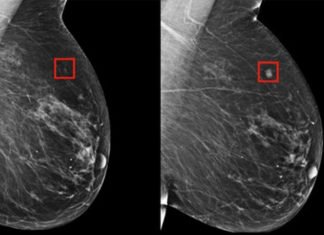

Dos productos químicos utilizados en cosméticos y cremas solares pueden favorecer el desarrollo del...

Un equipo de investigadores de la Universidad de Massachusetts (Estados Unidos), en un estudio publicado en la revista Environmental Health Perspectives, han identificado el mecanismo...